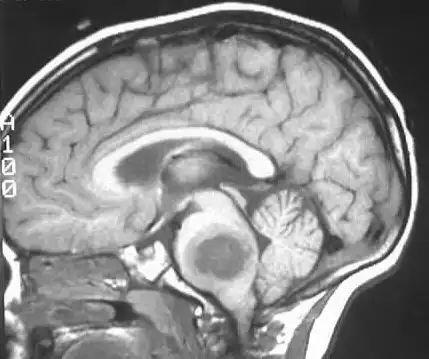

胶质瘤病人吃什么好

胶质瘤是近年来发病率比较高的一种疾病,严重危害着人们的身心健康和幸福生活。而术后饮食的话题也被更多的人们所关心,那么胶质瘤病人吃什么好呢?

相关图片